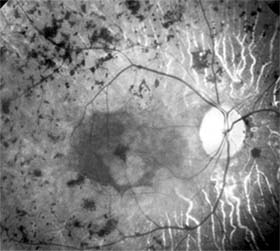

Figure 10-18: Retinopathy of prematurity with stretching of the macula and straightening of retinal vessels.

Retinitis pigmentosa is a group of hereditary retinal degenerations characterized by progressive dysfunction of the photoreceptors and associated with progressive cell loss and eventual atrophy of several retinal layers. The typical form of this disease can be inherited as an autosomal recessive, autosomal dominant, or X-linked recessive trait; one-third of cases will have a negative family history. The hallmark symptoms of retinitis pigmentosa are night blindness (nyctalopia) and gradually progressive peripheral visual field loss. The most characteristic ophthalmoscopic findings are narrowing of the retinal arterioles, mottling of the retinal pigment epithelium, and peripheral retinal pigment clumping, referred to as "bone-spicule formation" (Figure 10-19). While retinitis pigmentosa is a generalized photoreceptor disorder, in most cases rod function is more severely affected, leading to subjective sensations associated with poor scotopic function. The electroretinogram usually shows either markedly reduced or absent retinal function; the electro-oculogram lacks the usual light rise. The fundus appearance of retinitis pigmentosa may be mimicked by several disorders, including chorioretinitis, trauma, vascular occlusion, and resolved retinal detachment.

Figure 10-19: Retinitis pigmentosa with arteriolar narrowing and peripheral retinal pigment clumping.